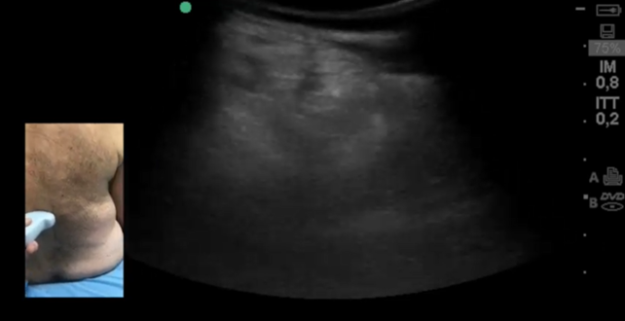

La pillola di dicembre, mostra la gestione del paziente già citato nell’argomento del mese. Riassumendo: paziente con via aerea difficile, intervento di stabilizzazione toraco-lombare, rinviato per intubazione fallita, con arresto…